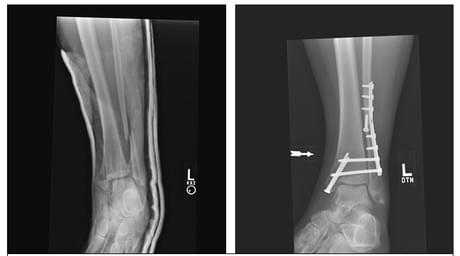

Пациент М. 1980 г.р., травму получил при падении на стопы с высоты 1,5 метра. Лечился по месту жительства (в травмпункте районной больницы) консервативно в гипсовой повязке в течение 14 дней. Консультирован в травматологическом отделении ФГБУ «УНИИТО им. В.Д. Чаклина» Минздрава РФ, предложено оперативное лечение. При поступлении кожные покровы стопы чистые, без признаков воспаления и сдавления тканей. Стопа отечна, уплощена. На рис. 1 представлены рентгенограммы пациента. Прооперирован через 2 недели после травмы. Операция состоит из двух этапов. Первый этап заключается в наложении дистракционного аппарата. Проводятся две спицы 1,8 мм во фронтальной плоскости: первая через нижнюю треть диафиза большеберцовой кости, вторая через бугор пяточной кости (рис. 2). Спицы фиксируются в дистракционном аппарате, выполненном из двух полуколец, соединенных между собой двумя телескопическими тягами. Особое расположение полуколец, фиксация спиц на концах полуколец, крепление кронштейнов для телескопических тяг обеспечивает тракцию пяточной кости в необходимом направлении с использованием минимального количества спиц и внешних опор при сохранении необходимого поля обзора для проведения рентгенологического и визуального контроля репозиции и фиксации. Второй этап - закрытая элевация импрессированной суставной поверхности и окончательная репозиция пяточной кости. Через разрез длиной до 1 см по латеральному краю ахиллова сухожилия (рис. 3) в месте его прикрепления к пяточной кости под соответствующий фрагмент подводится элеватор (рис. 4), манипуляцией которым устраняется смещение и выполняется провизорная фиксация спицами 1,5 мм (рис. 5). При сагиттальном раскалывании суставной фасетки целесообразно проведение одного-двух винтов субхондрально (рис. 6). Стержень вводится с дорзальной поверхности пяточной кости по ее оси через разрез до 2 см по предварительно сформированному остеотомом каналу (рис. 7, 8). Далее через проколы кожи с помощью кондуктора (рис. 9) выполняется запирание винтами с латеральной поверхности, внешнее устройство демонтируется. Достигнуто удовлетворительное стояние отломков (рис. 10).

Рис. 3. Под контролем ЭОП из разреза длиной до 1 см латеральнее места прикрепления ахиллова сухожилия выполняется элевация суставной поверхности пяточной кости

Рис. 4. Устранение смещения отломка

Рис. 5. Провизорная фиксация репонированной суставной поверхности спицами

Рис. 6. Окончательная фиксация компрессирующим винтом, введенным субхондрально